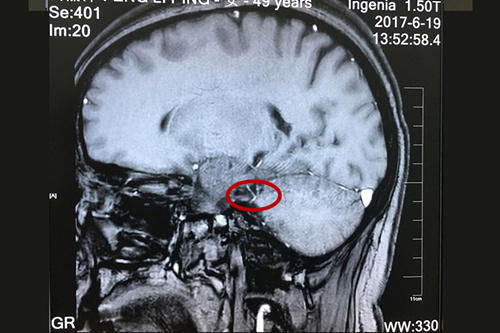

患者术前核磁显示:三叉神经和周围小血管关系密切,与之接触,并见骑跨。